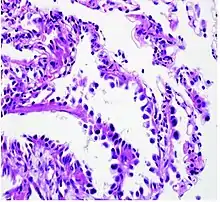

Adenocarcinoma of the lung tends to stain mucin positive as it is derived from the mucus-producing glands of the lungs. Similar to other adenocarcinoma, if this tumor is well differentiated (low grade) it will resemble the normal glandular structure. Poorly differentiated adenocarcinoma will not resemble the normal glands (high grade) and will be detected by seeing that they stain positive for mucin (which the glands produce). Adenocarcinoma can also be distinguished by staining for TTF-1, a cell marker for adenocarcinoma.[27]

As discussed previously, the category of adenocarcinoma includes are range of subtypes, and any one tumor tends to be heterogeneous in composition. Several major subtypes are currently recognized by the World Health Organization (WHO)[1] and the International Association for the Study of Lung Cancer (IASLC) / American Thoracic Society (ATS) / European Respiratory Society (ERS):[28][29][30] lepidic predominant adenocarcinoma, acinar predominant adenocarcinoma, papillary predominant adenocarcinoma, micropapillary predominant adenocarcinoma, solid predominant adenocarcinoma, and solid predominant with mucin production. In as many as 80% of these tumors, components of more than one subtype will be recognized. Surgically resected tumors should be classified by comprehensive histological subtyping, describing patterns of involvement in increments of 5%. The predominant histologic subtype is then used to classify the tumor overall.[2] The predominant subtype is prognostic for survival after complete resection.[31]

To reveal the adenocarcinomatous lineage of the solid variant, demonstration of intracellular mucin production may be performed. Foci of squamous metaplasia and dysplasia may be present in the epithelium proximal to adenocarcinomas, but these are not the precursor lesions for this tumor. Rather, the precursor of peripheral adenocarcinomas has been termed atypical adenomatous hyperplasia (AAH).[10] Microscopically, AAH is a well-demarcated focus of epithelial proliferation, containing cuboidal to low-columnar cells resembling club cells or type II pneumocytes.[10] These demonstrate various degrees of cytologic atypia, including hyperchromasia, pleomorphism, prominent nucleoli.[10] However, the atypia is not to the extent as seen in frank adenocarcinomas.[10] Lesions of AAH are monoclonal, and they share many of the molecular aberrations (like KRAS mutations) that are associated with adenocarcinomas.[10]